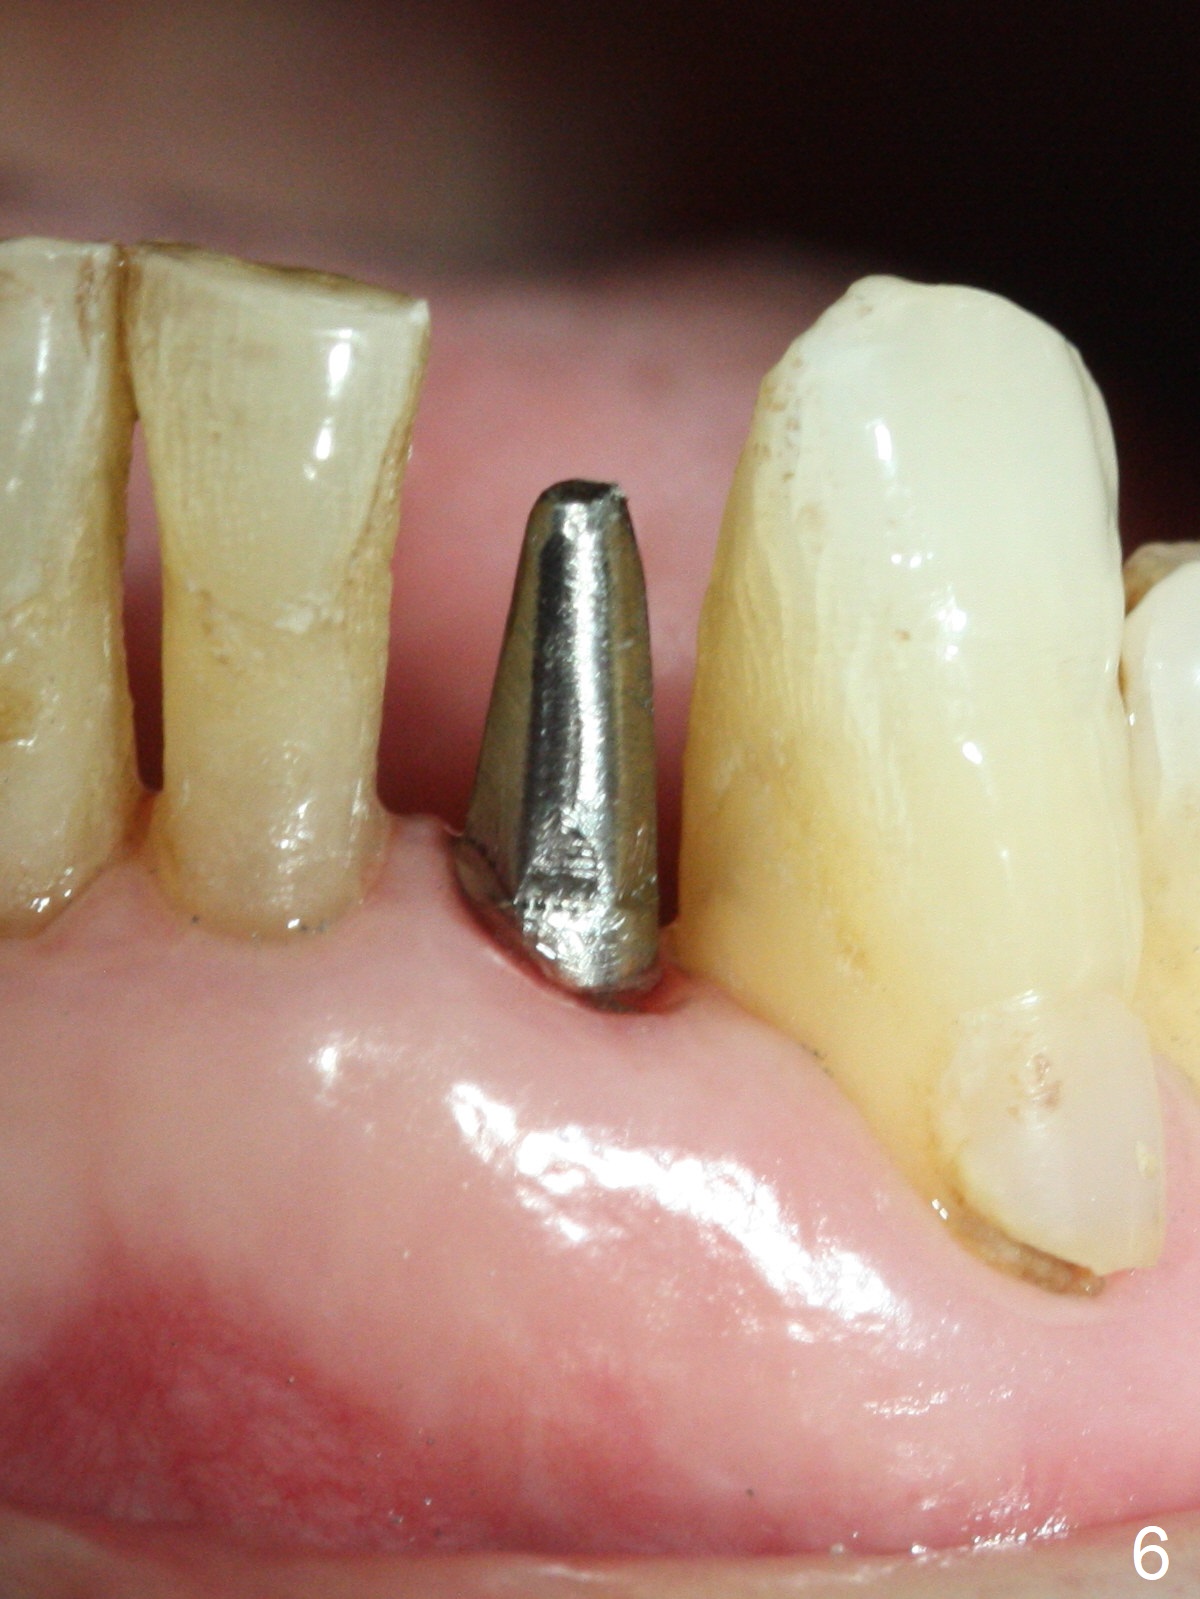

The tooth #23 is going to be extracted because the patient cannot masticate normally with mobility (Fit.1). The gingival depth is measured 2-4 mm after extraction. The 1st intraop PA taken with 1.2 mm drill for 16 mm shows the mesiodistal width is 5.11 mm (Fig.2); a 2.5x14(2) mm 1-piece implant is placed with >35 Ncm (Fig.3 with allograft placed). Following abutment preparation, an immediate provisional is fabricated to close the socket (Fig.4 P). There is no bone loss (Fig.5) or gingival inflammation (Fig.6 after reprep) 3 months postop. The narrow implant (2.5 or 2.0 mm) is indicated in the narrow edentulous space. The distal crest seems to be reduced in density and lower in height 1 year 7 months (Fig.7) and 1 year 11 months (Fig.8) post cementation. The severity does not worsen probably related to use of water pik. The crown looks bulky probably due to too large the abutment and too buccal placement of the implant (Fig.9, 10, as compared to Fig.1). A 2 mm implant may help?